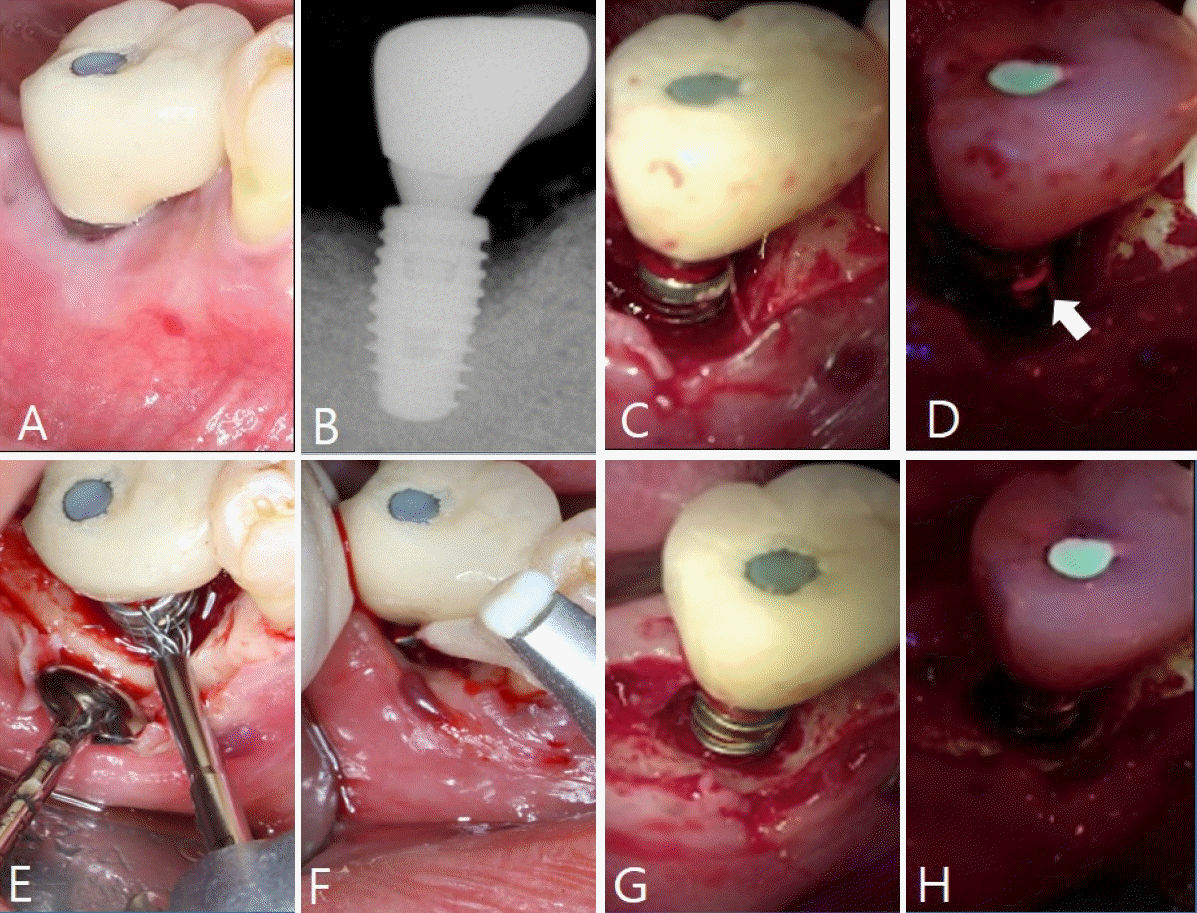

Figure 6.

A. Pre-treatment clinical photograph. B. Periapical standard radiograph. C. Clinical photograph after flap elevation. D. Quantitative light-induced fluorescence (QLF) image reveals biofilm on the implant surface (white arrow). E. Implant surface is decontaminated using a NiTi brush. F. Implant surface is decontaminated using an air-powder abrasive device. G. Clinical photograph shows the implant surface after decontamination. H. QLF image confirms a clean implant surface